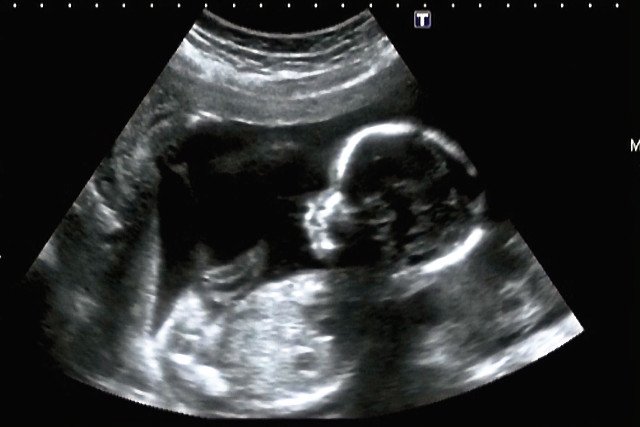

Jej stan jednak pogorszył się. Od trzech lat towarzyszyły jej ciągłe wymioty, nie miesiączkowała od pięciu. W końcu trafiła w ręce specjalisty z północnych Indii, dr Nilesha Junankara. Ten zleciał dokładne badania, które wykazały niedrożność jelit spowodowaną kamienną strukturą. To ona blokowała układ trawienny. W brzuchu kobiety znaleziono czteromiesięczny, skamieniały płód. Operacja usunięcia trwała dwie godziny. Sam lekarz przyznał, że był zdumiony, bo to niezwykle rzadka sytuacja.

Lithopedion, bo tak nazywa się zwapnienie płodu. Na świecie w ciągu 400 lat zgłoszono 300 takich przypadków. Ciąża brzuszna zdarza się raz na 11 tys. ciąż i tylko 1,5 do 1,8 procenta z nich "kamienieje".

Najczęściej kobieta nawet nie zdaje sobie sprawy, że jest w ciąży, więc nie wie, że w jej ciele znajduje się płód, który obumarł. Organizm nie radzi sobie z wydaleniem czy wchłonięciem powstałego tworu, więc aby uniknąć zakażenia otacza go wapienną powłoką.